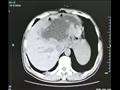

وذهب "شاي" إلى المستشفى بعد أربعة أشهر، عقب معاناته من قشعريرة وحمى شديدة لمدة ثلاثة أيام. وذهل الأطباء عندما اكتشفوا أن كبد المريض يحتوي على كتلة ضخمة مليئة بالصديد يبلغ طولها 19 سم وعرضها 18 سم، وفقا للتقرير.

وحاول الجراحون في البداية تقليل النتوء الاجتياحي مثل الكيس، عن طريق تجفيف الكتلة من السوائل، ولكنهم أدركوا بسرعة أن العدوى شديدة جدا، وقرروا قطع نصف الكبد.

وكشف فحص لاحق أن الكتلة كانت تحتوي على عدد لا يحصى من البيض الذي وضعه متفرع الخصية الصيني أو وشيعة الكبد الصينية، وهو طفيل موجود في المأكولات البحرية النيئة.